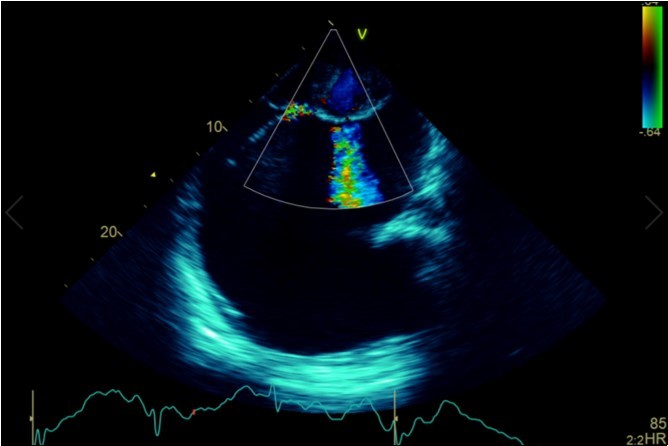

A dramatically dilated left atrium was seen on a TTE (see Figure 2a, Figure 2b, Figure 2c, and Figure 2d). Severe mitral stenosis with associated regurgitation was evident, with a mean gradient across the valve of 11mmHg and a hyperdynamic left ventricle. The left atrial volume measured by Simpson’s biplane method (see Figure 2c) was 2108mL, or 1548.5 ml/m2, based on height 1.55 metres and weight 44 Kg. Normal left atrial volume in a woman is 16 - 34 ml/m21. The computed tomography scan (CT) chest AP view (see Figure 3) is also shown.

Figure 2a.Transthoracic echocardiogram Apical 4C view. Findings include severely enlarged left atrium, severe mitral stenosis with associated regurgitation, a mean gradient across the valve of 11mmHg with a hyperdynamic left ventricle

Transthoracic echocardiogram Apical 4C view. Findings      include severely enlarged left atrium, severe mitral stenosis with                  associated regurgitation, a mean gradient across the valve of 11mmHg with a hyperdynamic left ventricle